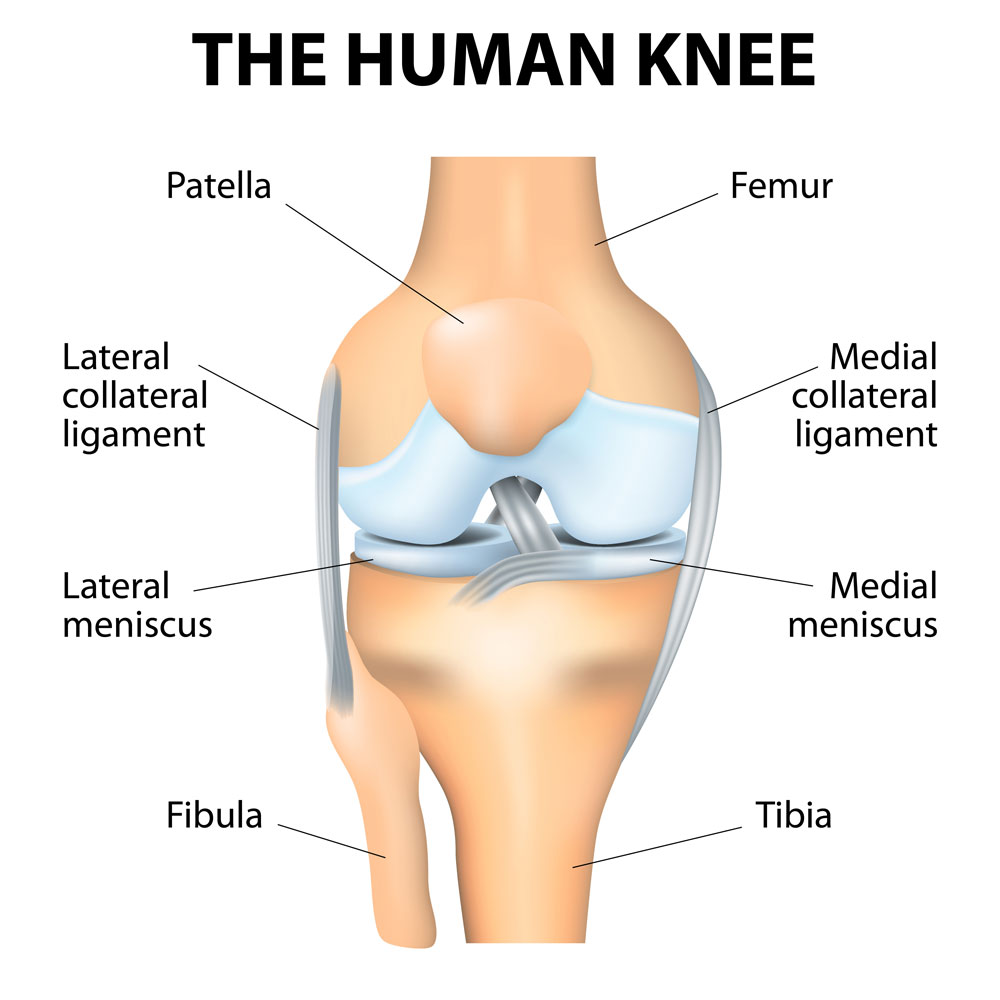

Рисунки Суставов: Анатомические Иллюстрации